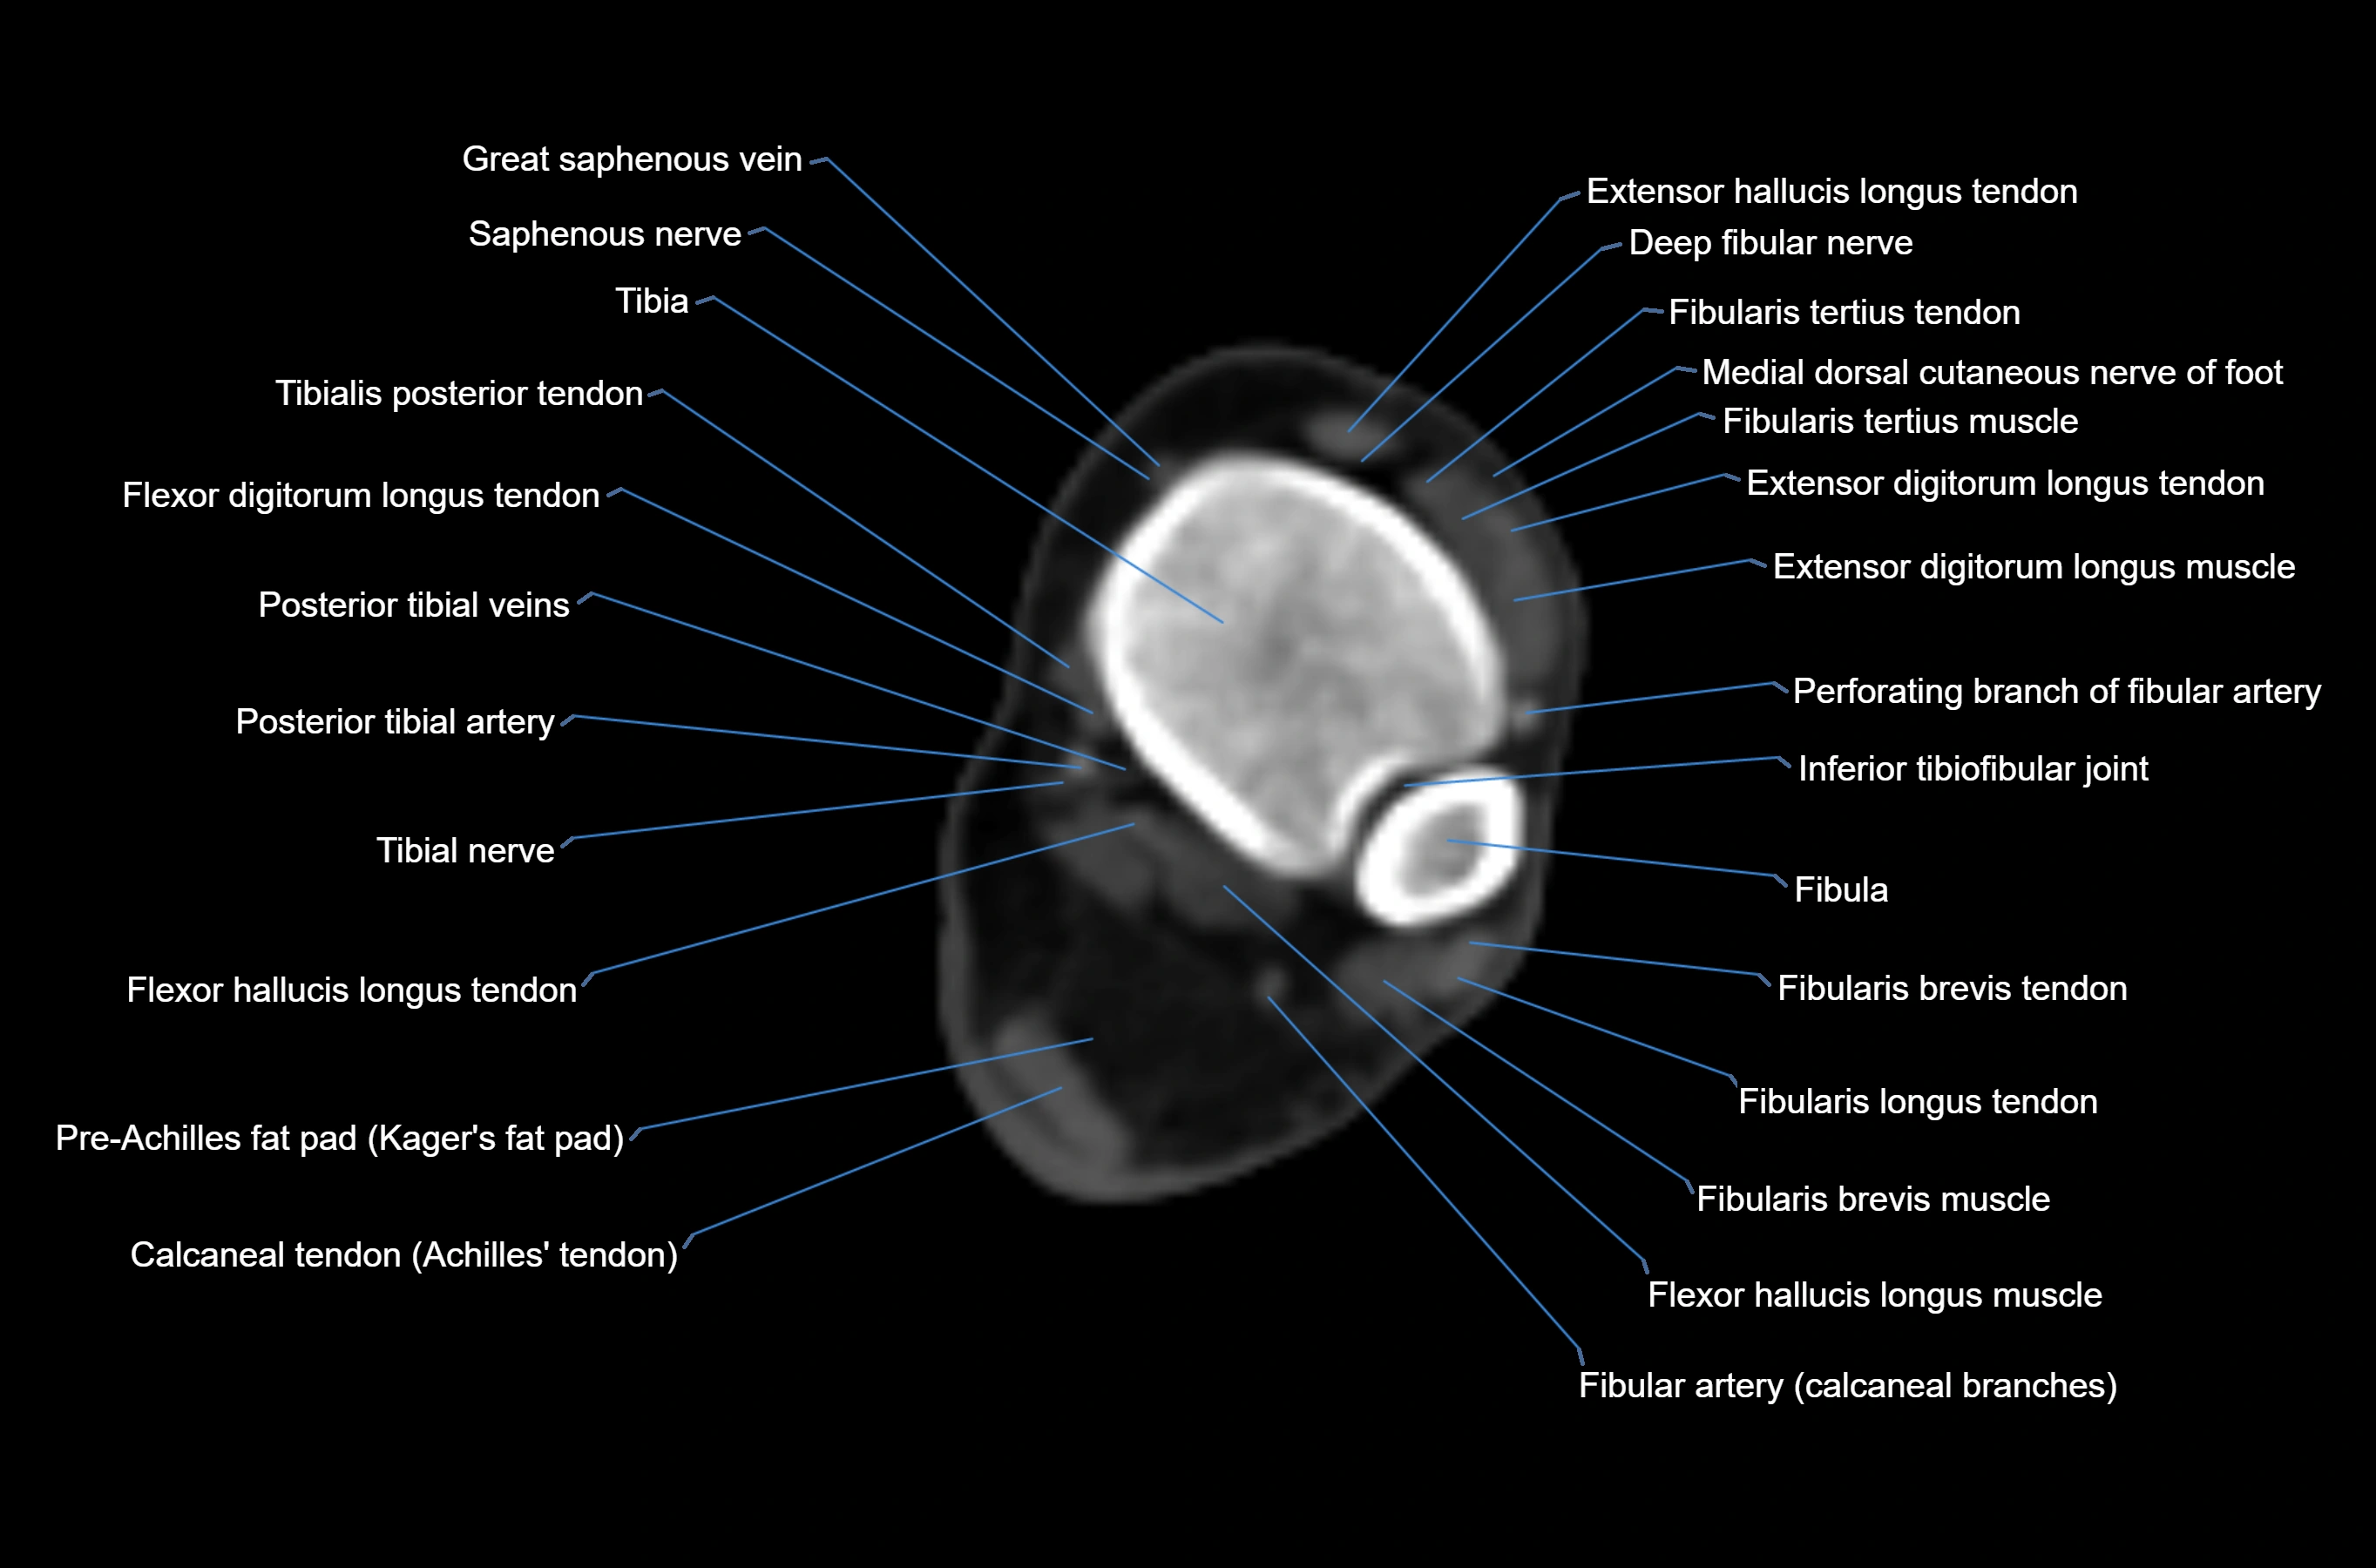

CT image